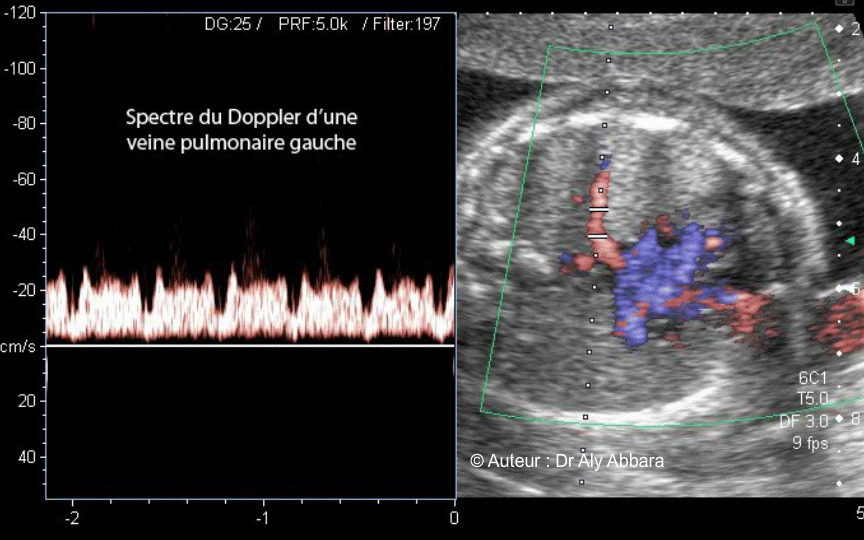

Image échographique montrant le spectre du Doppler d'une des deux

veines pulmonaires gauches.

- Le spectre du Doppler des veines pulmonaires (retour pulmonaire vers l'oreillette gauche) est composé de deux pics (S et D) et d'une incisure (a), ces composants correspondent dans le cycle cardiaque aux phases suivantes :

- Pic (S) = systole ventriculaire gauche

(contemporaine du remplissage de l'oreillette gauche)

- Pic (D) = diastole ventriculaire gauche

(ouverture de la valve mitrale)

- Notch (incisure) a = contraction de l'oreillette gauche (atrial systole)

- Ce spectre est aussi le reflet des pressions veineuses fœtales qui dominent dans l'oreillette gauche.

- Ce spectre ressemble (pour le mémoire) à l'ombre laissée par la tête du personnage de fiction " Batman ".